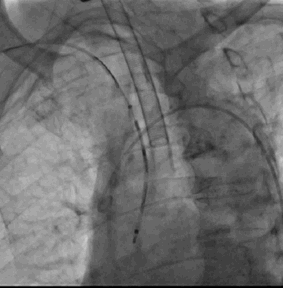

1. 患者于全麻下行LAAO术,常规消毒铺巾,经右桡动脉置入6F Sheath,右侧股静脉置入6F Sheath,左股动脉置入5F Sheath,5F pigtail后行主动脉弓造影

2. 经右桡动脉置入Sentinel CPS系统,释放于头臂干、左颈总动脉位

3. 经右侧股静脉置入SL1鞘管,沿鞘管送入房间隔穿刺针,食道超声下见左心耳血栓

4. 超声指导下成功行房间隔穿刺,将鞘管推进至左房后予肝素7000U,SL1 导丝送左房后,超声下测左心耳开口大小后选用LAmbre 左心耳封堵器(20-26mm)

5. 超声及造影下见封堵器放置位置良好,二尖瓣及肺静脉段未见影响,测试位置固定后释放封堵器